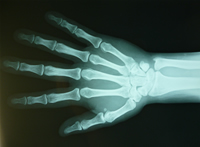

ピアニストも手に負担が掛かる為腱鞘炎に悩んでいる奏者も後を絶ちません。

音楽の障害についての講義を大学(声楽科)、各楽器奏者、大阪フィルハーモニー交響楽団、日本センチュリー交響楽団、宝塚歌劇団等の方々に実技とストレッチ指導を交えて行って参りました実績により、各楽器に即した『ピアノなら手を中心としたストレッチ』と解剖学と医学的な知識を持っております。

ピアニストの有痛性痙攣は、手に多くの負担がかかったために現れます。

指や手首の伸筋が痙攣して、痛みに襲われます。

筋力も低下し、筋肉の機能異常が現れることがあります。

また腱の炎症を伴う場合もあります。